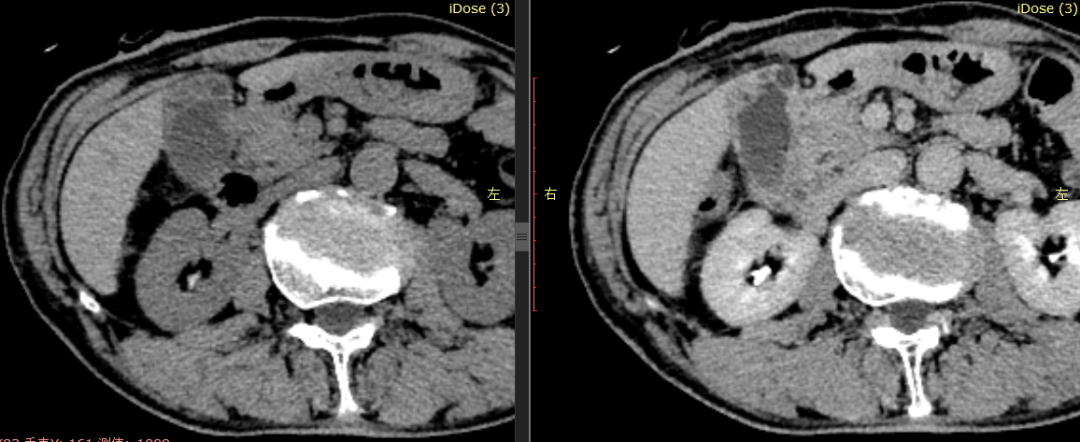

CASE 3